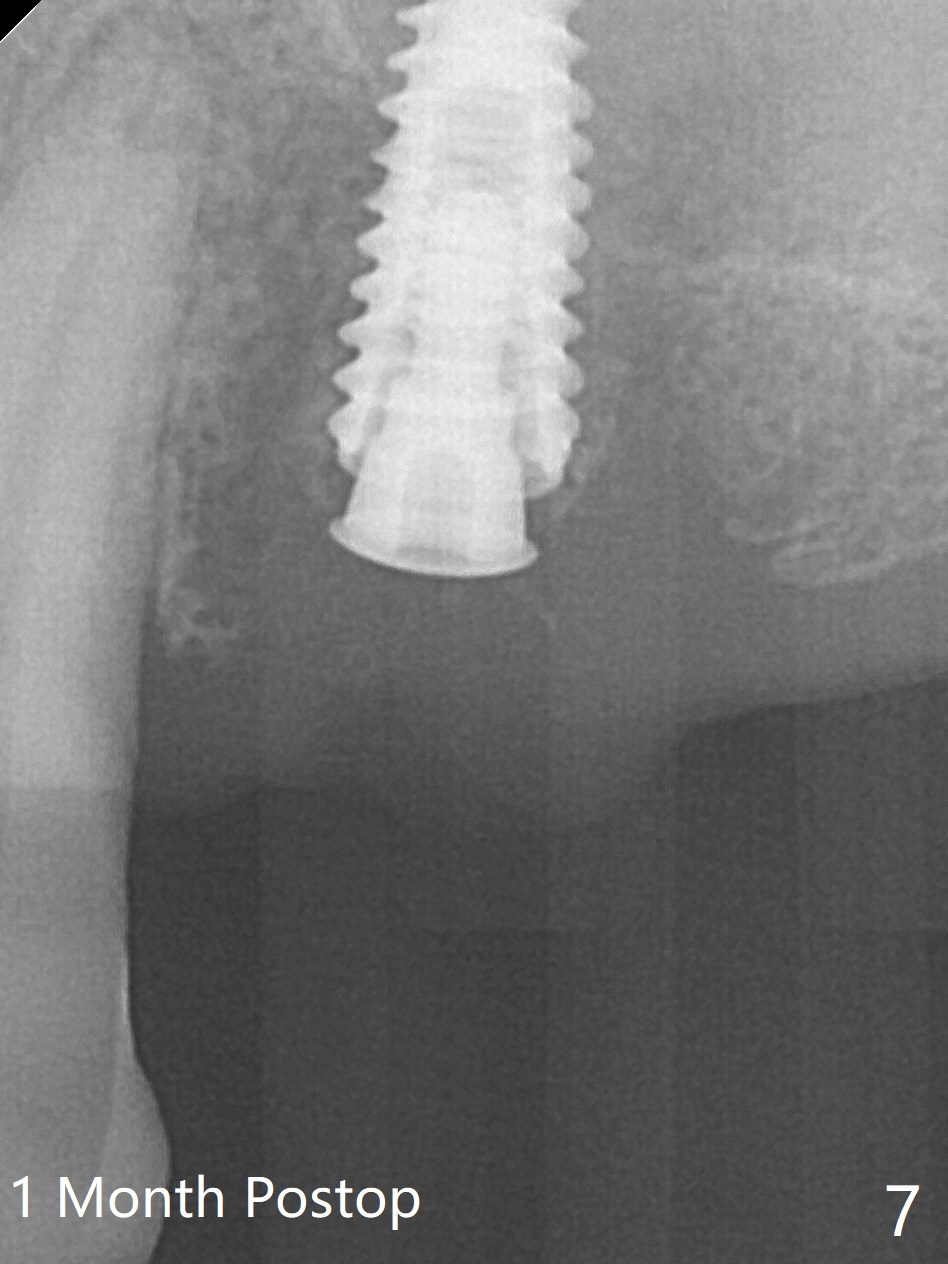

After a 4x10 mm implant is placed with fixture mounting (Fig.2 M) following sinus lift (*) at #12, osteotomy is initiated at #10 (Fig.1 (T: tube of surgical guide)). It appears that the drill (D) has good trajectory (between the Incisive Canal (red dashed line) and the canine root). The final position of the implant at #10 is acceptable (Fig.3). The implant at #12 is placed deeper (Fig.4 (arrow), as compared to Fig.2) because of clinically buccal superficial placement. The most critical challenge is anterior deep bite associated with posterior collapse. Periodontal dressing is applied. When the latter dislodges, there is minimal clearance for a provisional. Periodontal dressing is re-applied. The patient (smoker, partial edentulism with occlusal interference) returns for provisional nearly 1 month postop with chief complaint "something is lost in the back". In fact the healing abutment at #12 is lost with buccal granulation tissue (Fig.5). When a new abutment is seated, there is discomfort. When a healing screw is placed, it cannot be seated completely with two separate trials (Fig.6,7). Should we leave it as it is or open up for complete seating? It appears that the implant is loose. After preparation for clearance at #10, the abutment is retightened. It appears to turn with the underlying implant with discomfort. A 4x5 mm healing abutment is placed to reduce micro-movement. One week later, the infection at #12 dissolves with oral Amoxicillin (Fig.8). Due to limited occlusal clearance and implant tenderness when the abutment abutment is retightened, the cemented abutment is changed to a healing abutment. The implant at #10 seems to be osteointegrated, while the healing screw at #12 remains incomplete seating 3 months postop (Fig.9). The loose healing screw cannot be retightened securely, as there is bone loss around the implant 3 months postop (Fig.10 *). When a 4.5 mm x 15 degree 4 mm cuff angled abutment is placed, the mesiodistal trajectory improves (Fig.11), but there is no occlusal clearance (Fig.12). The latter would form when posterior support is established (Fig.13, either removable appliance (which the patient hates) or fixed one (finance)). Fig.14 shows the unhealed site of #12. Incision confirms the bone loss around the implant, which is removed. Although the sinus floor is absent, there is no membrane perforation. After debridement, allograft mixed with small amount of Osteogen is placed (Fig.15,16 G) and covered with Osteogen plug and 6-month membrane.